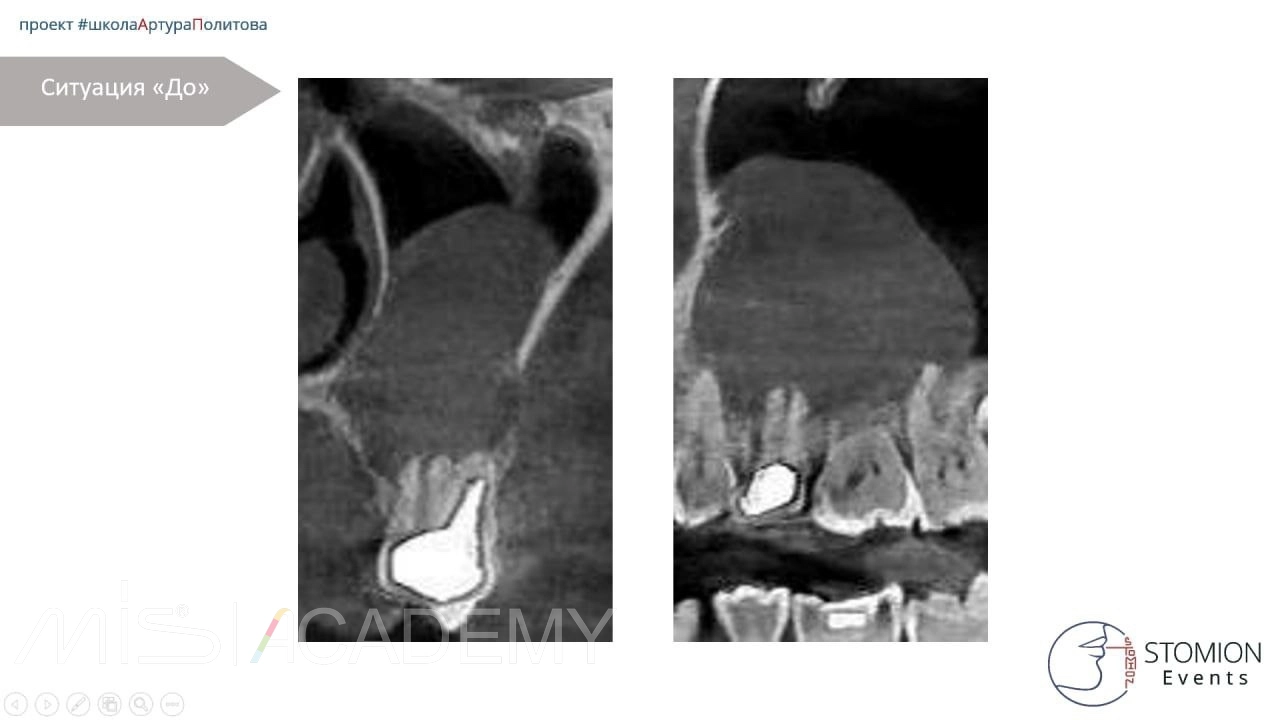

— Провели КЛКТ и анализ полученных данных. Обнаружена корневая киста примерно 26х28мм от зуба 2.5.